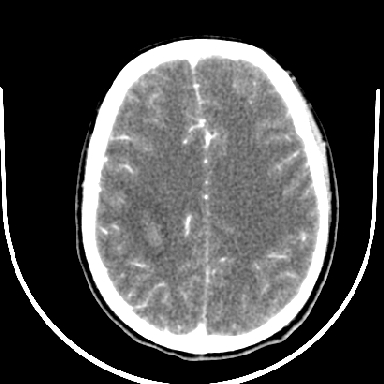

标题: CT6056:脑出血(血管畸形?) [打印本页]

标题: CT6056:脑出血(血管畸形?)

m 40突发头痛左侧偏瘫3小时